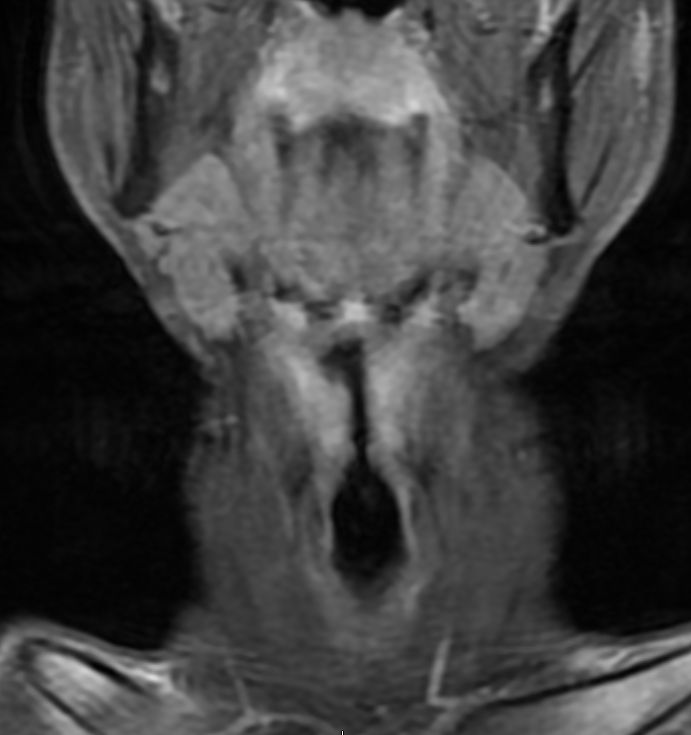

MRT: supraglottisch T3 No |

57-jähriger Mann mit langjährigem Alkohol- und Nikotinabusus. Seit 6 Monaten Schluckbeschwerden. Jetzt zunehmende Kachexie. MRT: Ausgedehntes supraglottisches Larynxkarzinom mit Schildkrorpel-Infiltration. Kehlkopfteilresektion mit ND. Histologie: unverhornendes Plattenepithelkarzinom, V0 R1 G1 - 2 Stadium post OP: pT3 pN0 (0/7) M0 | ||